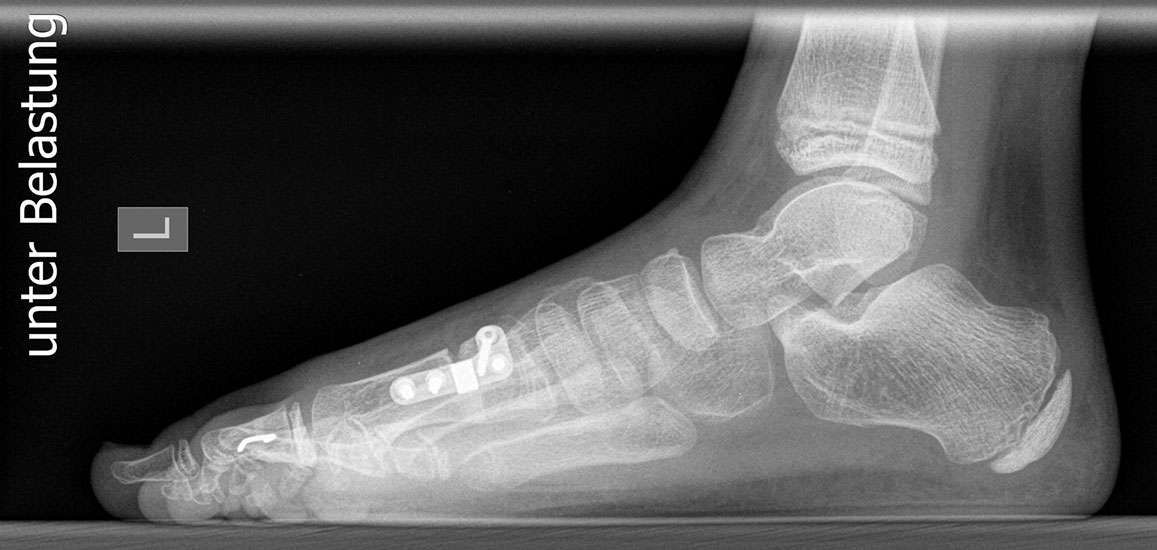

Standard ist die belastete Röntgenaufnahme des Fußes dorso-plantar und seitlich. Günstig ist eine Röhrenkippung von 10°-20°, um die Gelenke der Lisfranc-Linie einsehen zu können.

Ergänzend kann eine Schrägaufnahme hilfreich sein. Bei Metatarsalgien oder Pathologien der Sesambeine liefert die Sprinteraufnahme zusätzliche Informationen. Bei einer Pes planovalgus Fehlstellung wird ergänzend ein Saltzman view durchgeführt.